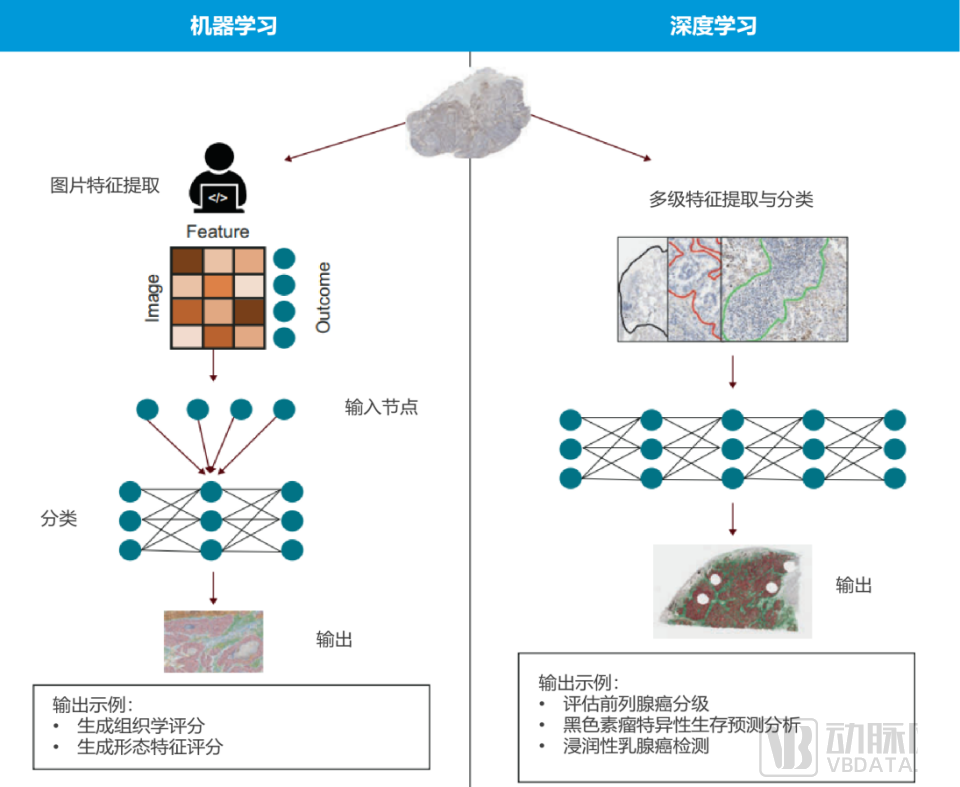

工作流程对比图

工作流程对比图

来源:商汤科技